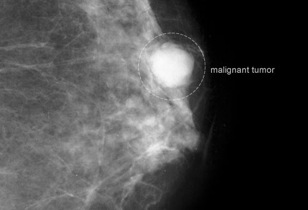

Καρκίνος του μαστού

Όσο

νωρίτερα διαγνωστεί ο καρκίνος του μαστού, τόσο υψηλότερα είναι τα

ποσοστά επιτυχούς θεραπείας. Εάν βρεθεί σε αρχικό στάδιο είναι

μικρότερες οι πιθανότητες ο καρκίνος να έχει επεκταθεί στους λεμφαδένες

και σε ζωτικά όργανα όπως οι πνεύμονες και ο εγκέφαλος. Στις ηλικίες των

20 και των 30 ετών, ο έλεγχος των μαστών πρέπει να συμπεριλαμβάνεται

στο τακτικό σας check up, κάθε 1-3 χρόνια, ή και συχνότερα εάν υπάρχουν άλλοι παράγοντες όπως το βεβαρημένο ιστορικό που το απαιτούν. Ο Υπέρηχος Μαστού είναι

μία διαγνωστική μέθοδος ανώδυνη και ακίνδυνη (δεν υπάρχει κανενός

είδους ακτινοβολία) και μπορεί να επαναλαμβάνεται όσο συχνά χρειάζεται

άφοβα. Αφορά τη χρήση υπερήχων για τον πλήρη έλεγχο του μαστού και της

μασχαλιαίας χώρας (έλεγχος λεμφαδένων αυτής). Σε ηλικίες άνω των 40 ετών

κάθε χρόνο απαιτείται μαστογραφία. Βέβαια την συχνότητα με την οποία θα

πρέπει να ελέγχονται οι μαστοί σας θα την καθορίσει ο γιατρός σας

ανάλογα με το ιστορικό σας.